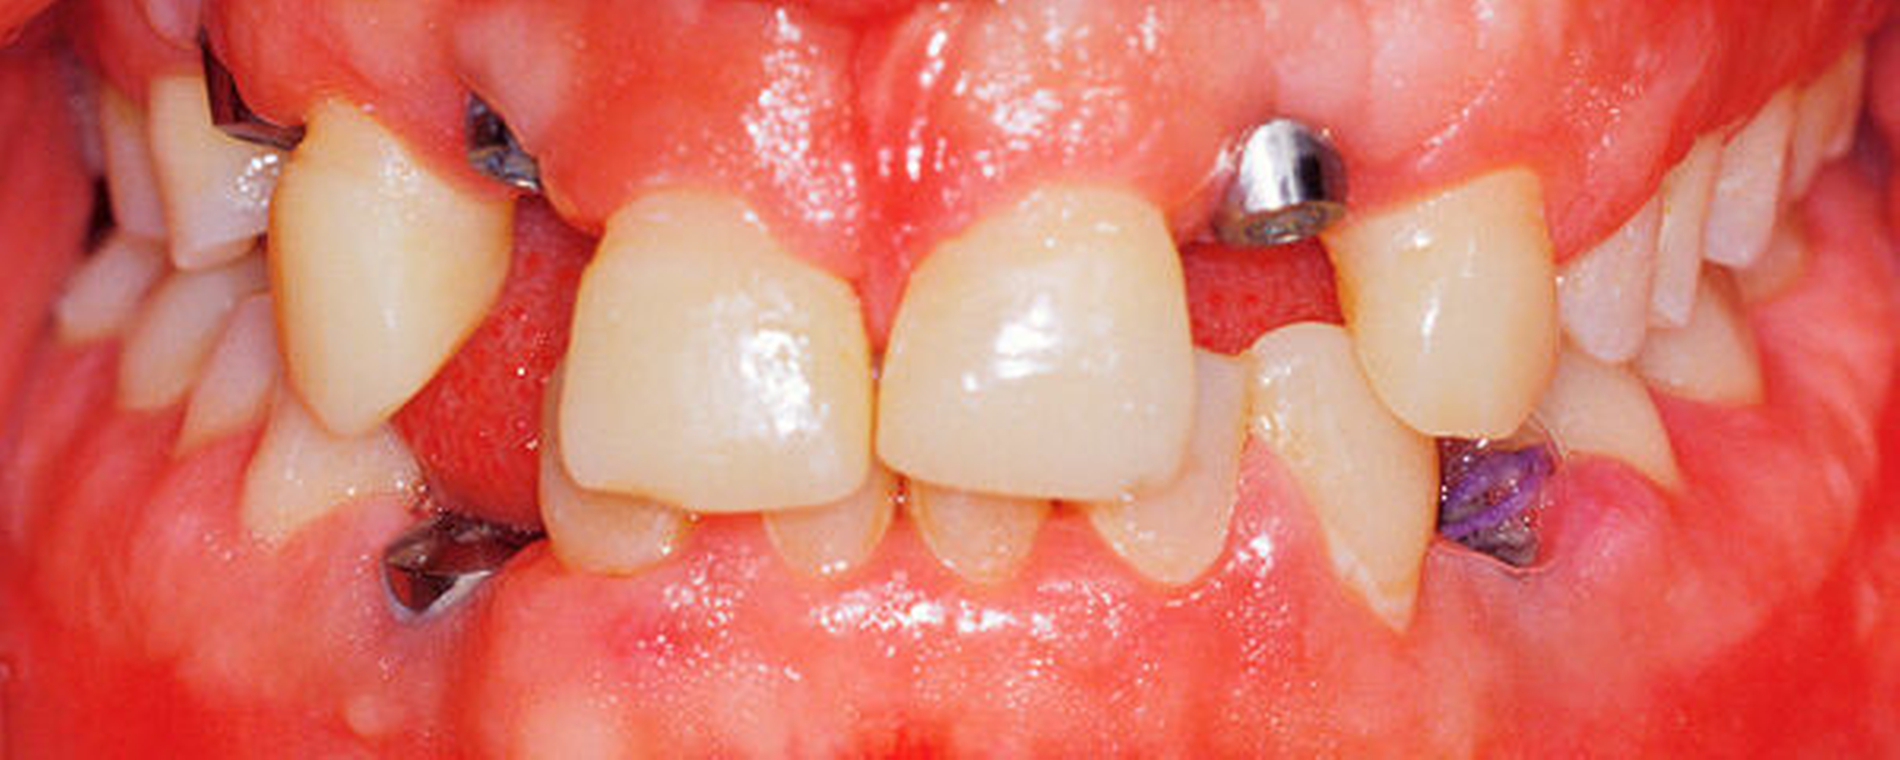

In mehreren Schritten wurden circa vier bis zwölf Monate später in Lokalanästhesie Implantate in den Regionen 12 und 22 (Straumann Narrow Neck) sowie 14, 33 und 44 (Straumann Regular Neck) gesetzt (Abbildung 8a). Zur Verlängerung der kurzen klinischen Kronen 11 und 21 wurde in diesem Bereich die Gingiva im Sinne einer Konturierung elektrotomiert (Abbildung 8b).